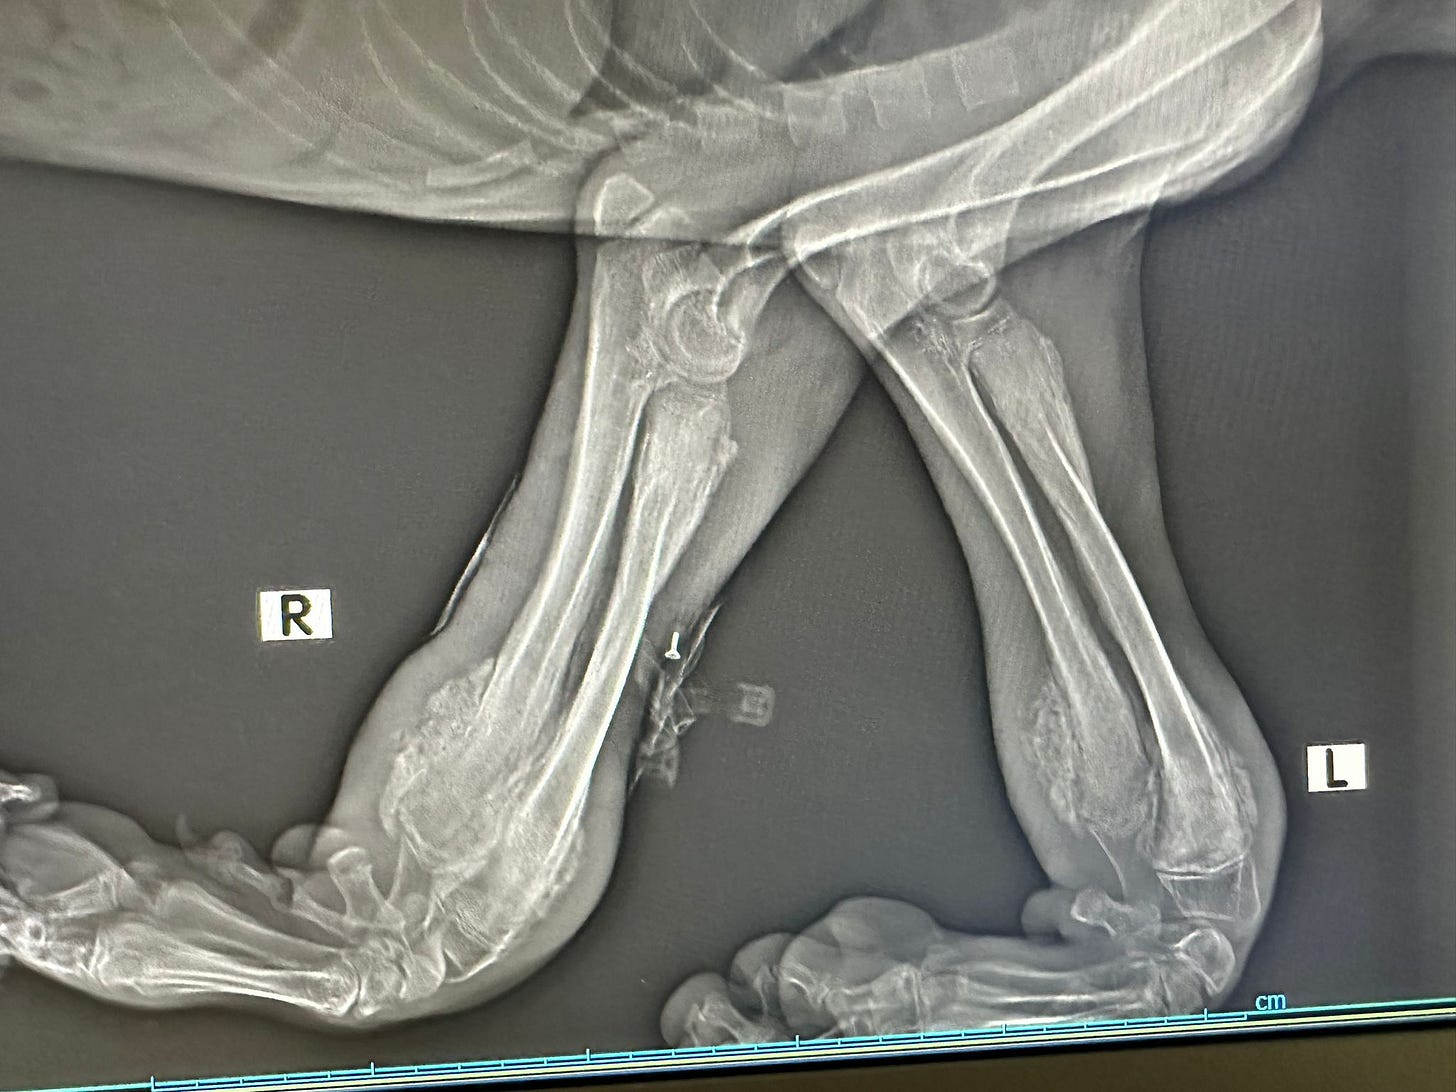

The stiffness in Milo’s leg, which we mentioned earlier, was eventually traced to a failed surgical plate.

Sadly, while not common, plates can sometimes fail, and in Milo’s case it caused further complications. A replacement plate was fitted, but damage to the surrounding muscle from the original procedure meant that his recovery was severely hindered.

For months, Milo struggled to carry the useless limb, which was clearly slowing him down and preventing him from thriving. After much thought and discussion, we made the difficult but compassionate decision to amputate.